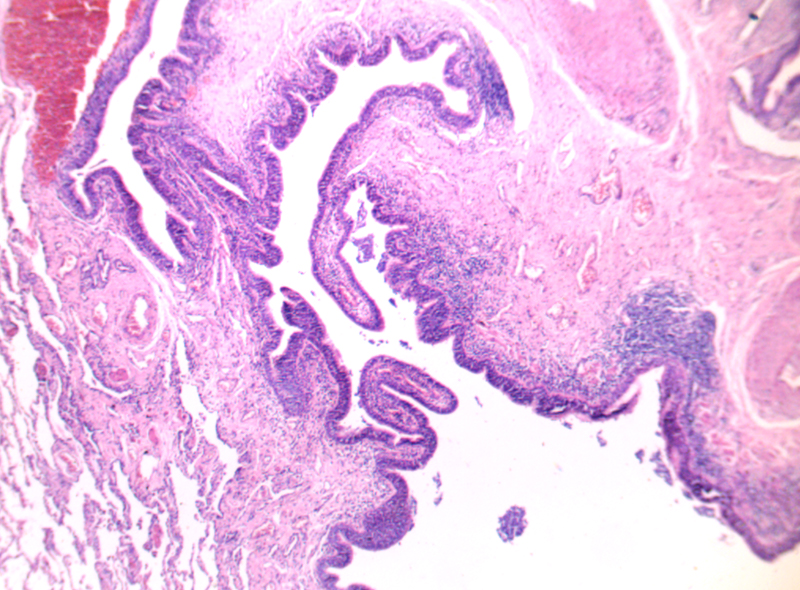

潰瘍